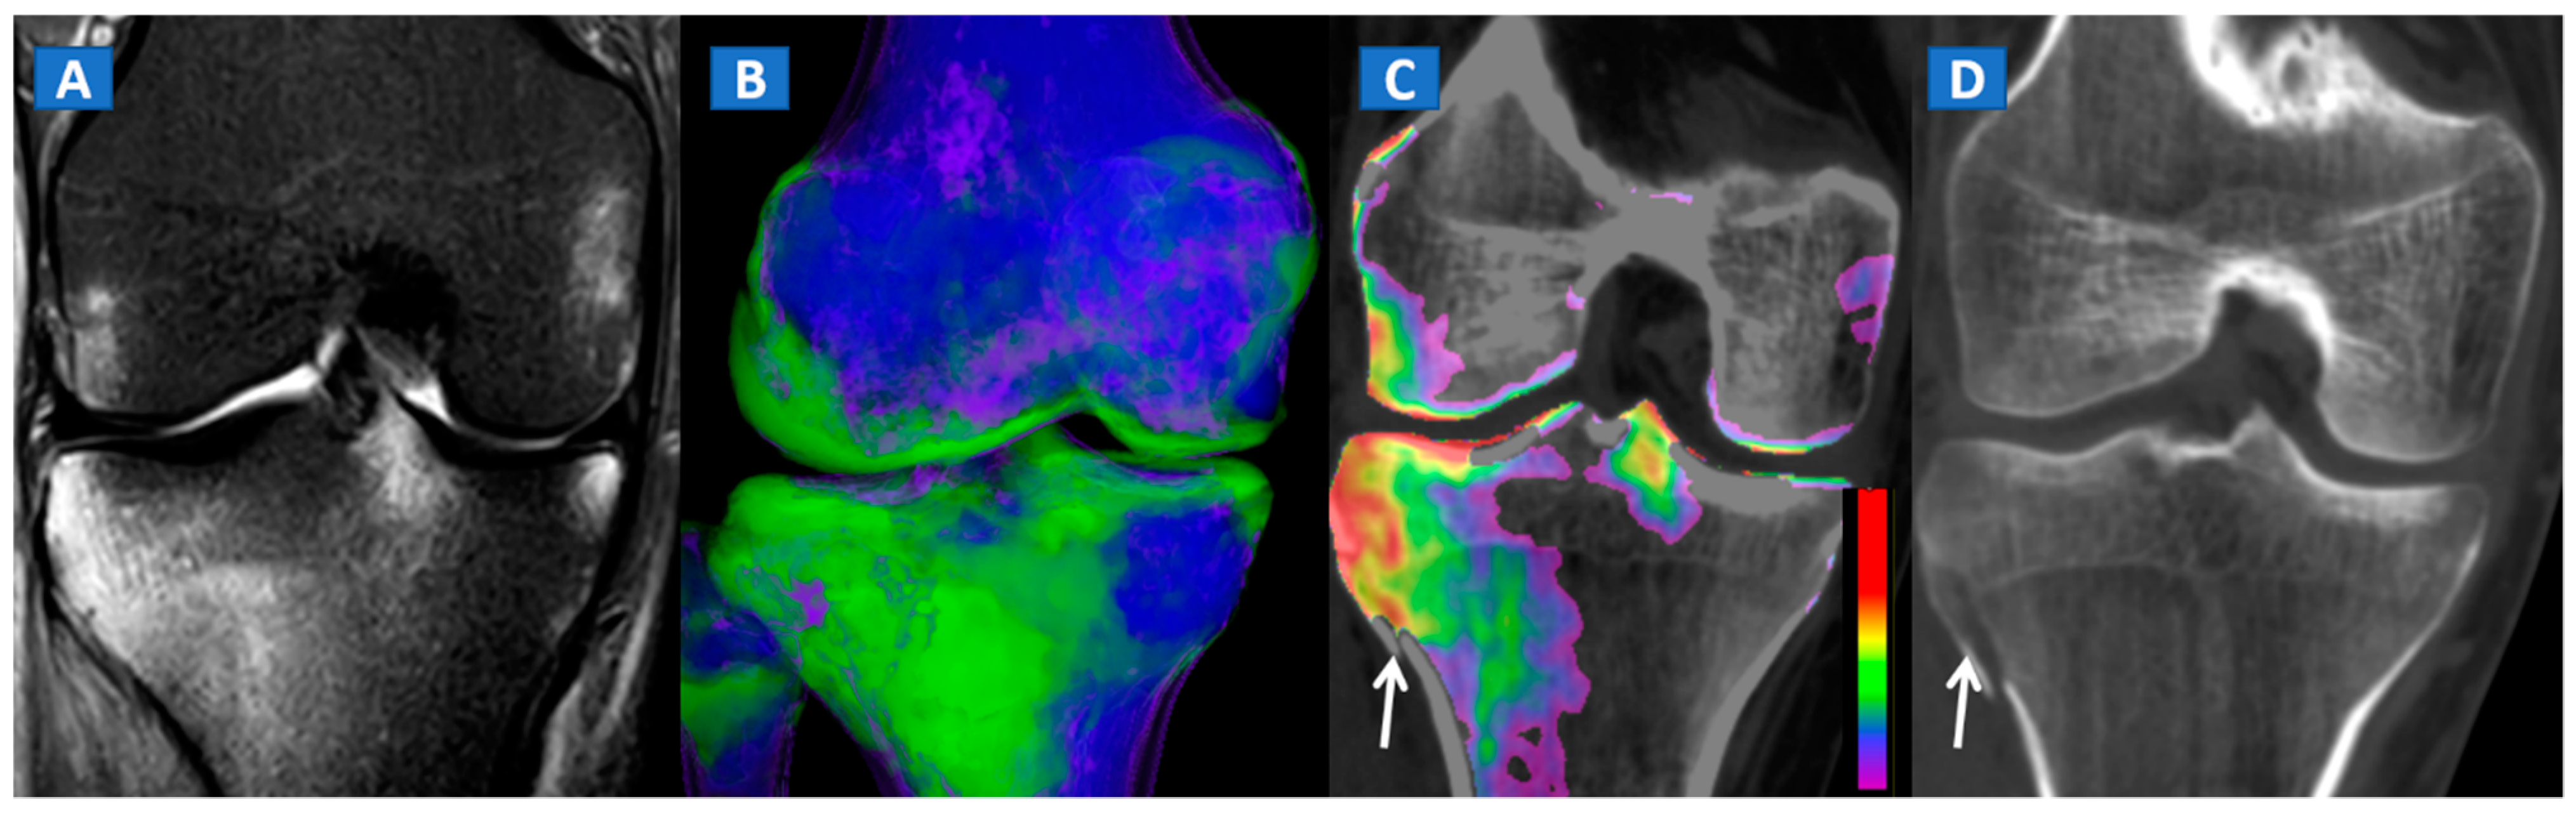

Figure 7.

A 44-year-old male with post-traumatic OCL of the talar dome. On the coronal STIR MRI image (A), a hyperintense subchondral area of BME is depicted on the medial aspect of the talar dome (arrow), which is consistent with the diagnosis of OCL of the talus. The lesion appears hypointense on the T1-weighted images ((B); arrow). On the 1 mm reconstructed 2D coronal DECT image (C) and coronal 3D DECT map, the lesion appears as a subchondral oedematous area (arrow), due to its increased water content. On the corresponding 3D image (D) the BME is coded in green (arrow).